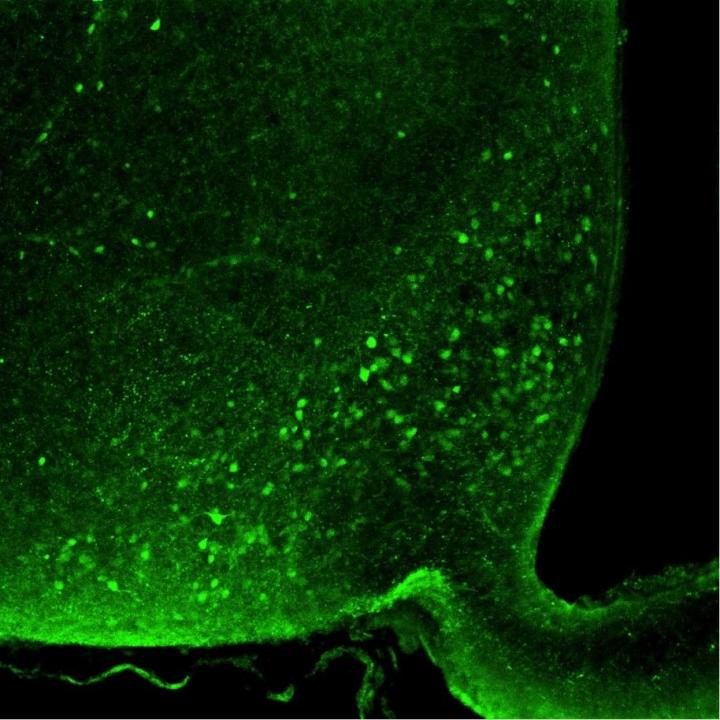

image: Nociceptin neurons in the arcuate nucleus of the hypothalamus.

Since the 1980s, we are seeing a worldwide increase in obesity and associated diseases such as diabetes mellitus and cardiovascular disease. Researchers from the Max Planck Institute for Metabolism Research from the laboratory of Jens Brüning have used mice in animal studies to investigate which nerve cells control the overeating of high-calorie, energy dense food. For this purpose, the animals were fed a high-fat diet and examined afterwards." Just three days of a high-fat diet feeding were sufficient to detect increased activity of nociceptin neurons in a specific region of the brain, the arcuate nucleus of the hypothalamus," says Alexander Jais, first author of the current study.